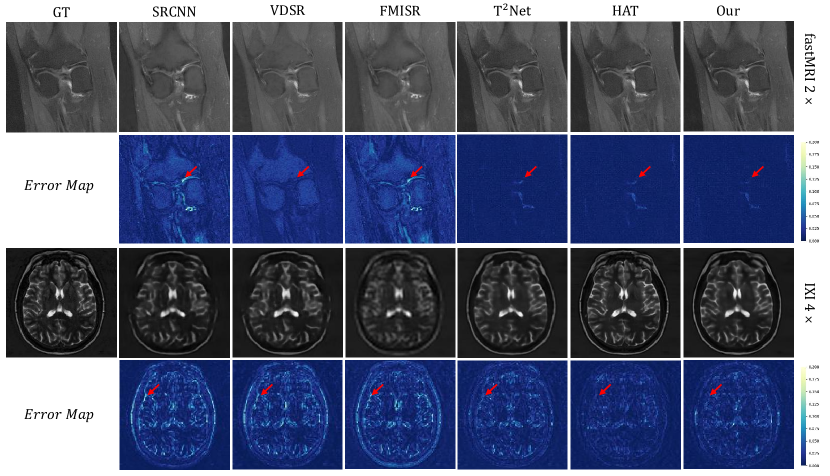

Refer to caption

Figure 2: Qualitative results with different methods under fastMRI and IXI dataset

Qualitative Analysis. The super-resolved results and corresponding error maps are shown in Fig.2 under the fastMRI and IXI datasets. The error map is typically a visualization of the difference between the super-resolved image and the ground truth high-resolution image. The darker the color, the smaller the difference between the generated image and the label image, and vice versa. The figures show that the compared methods on the fastMRI dataset produce blurring artifacts since the available information in the image is not fully utilized by these approaches. It can be clearly seen in the error map that the color of our method is the darkest. For the IXI dataset, our method with fewer parameters achieved the best local visualization results.